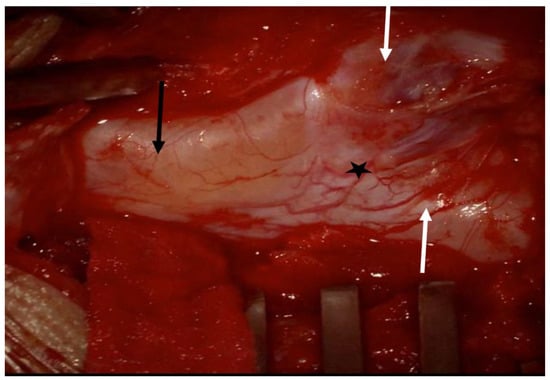

2. Clinical Presentation